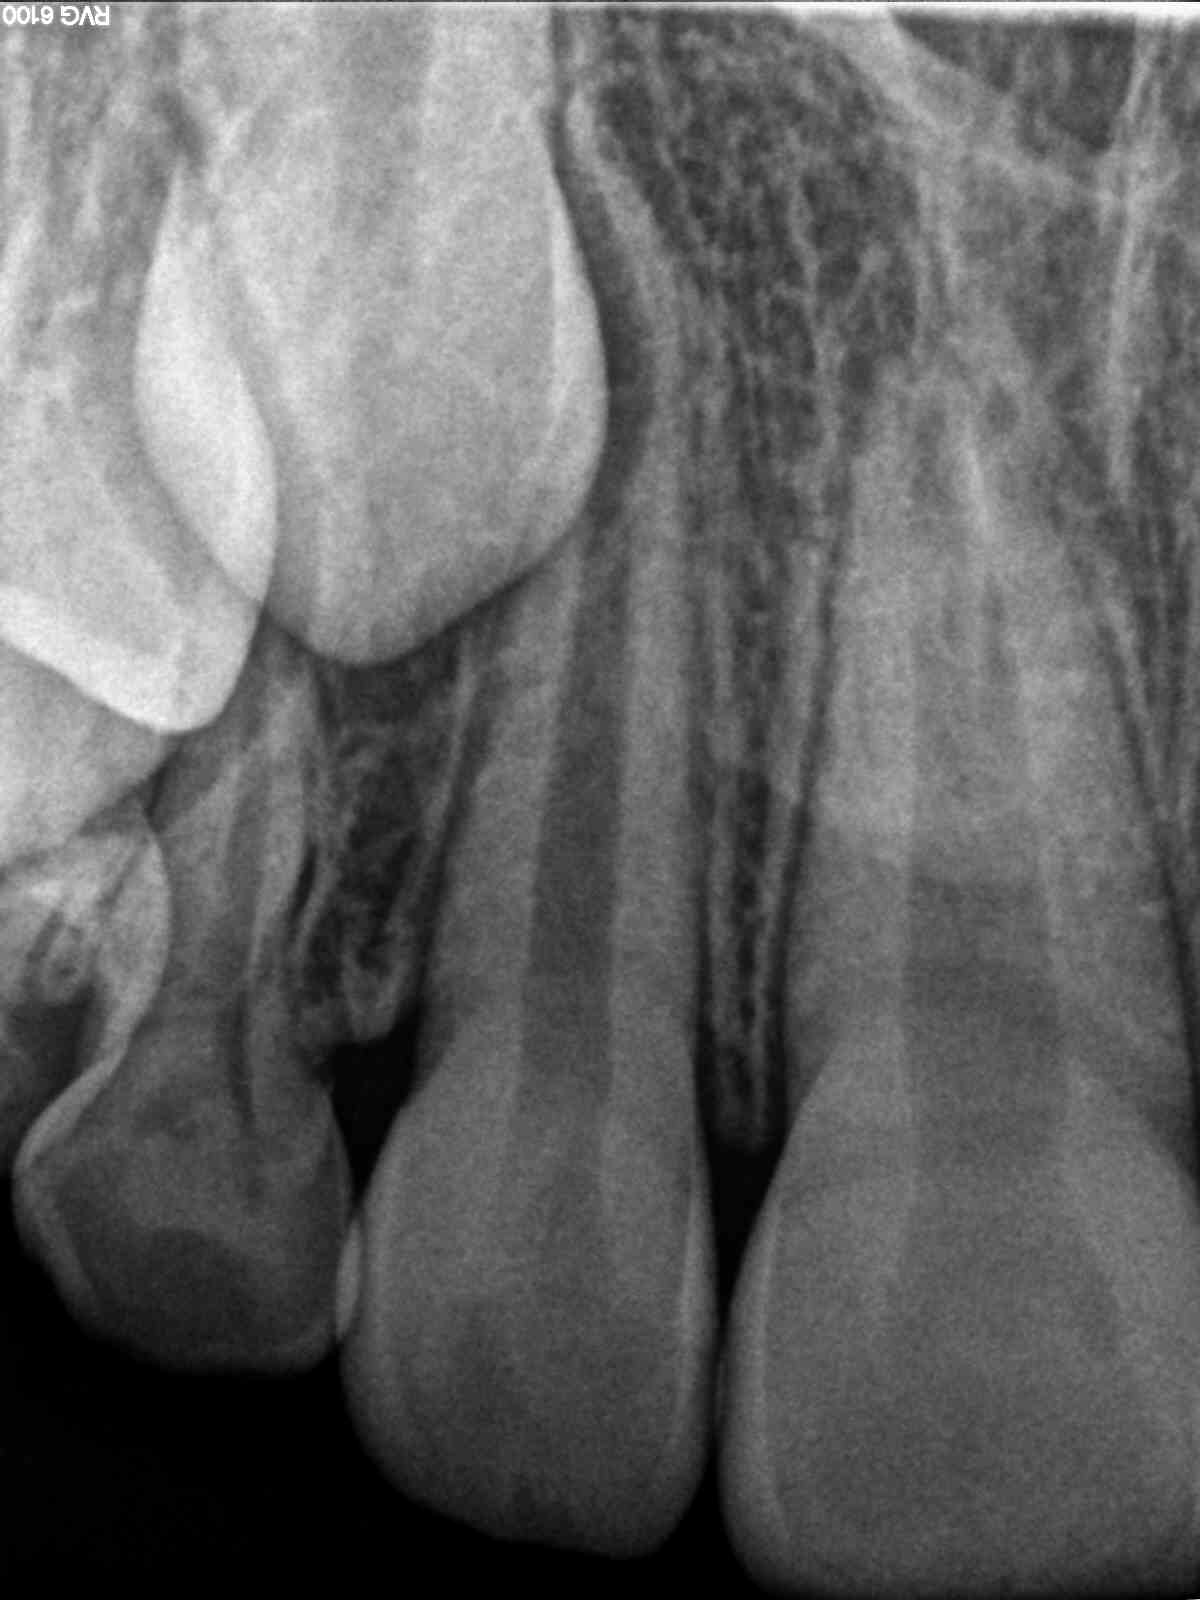

R2

Revival